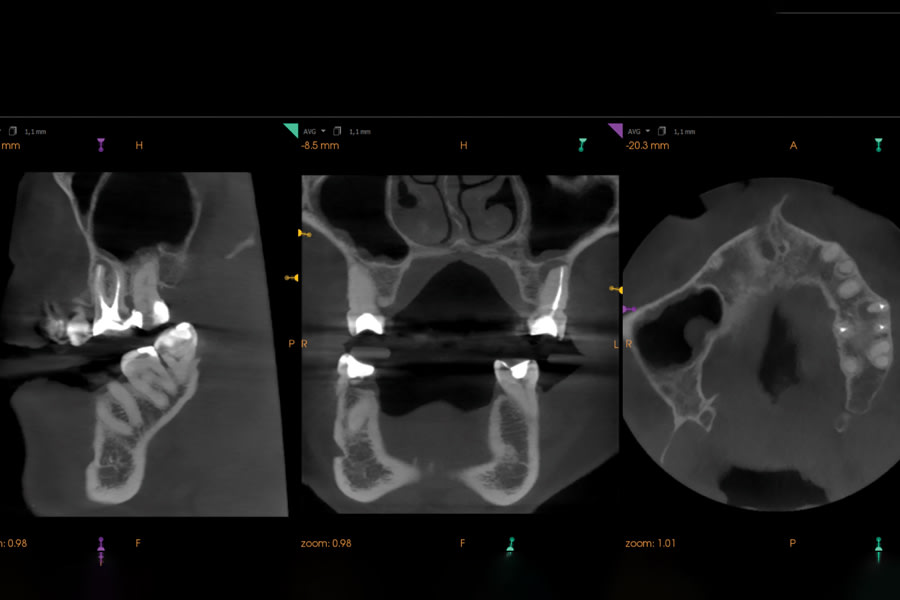

This case illustrates the value of contemporary reciprocating systems in addressing anatomical variations that can compromise primary endodontic success. A 62-year-old female patient was referred to the author’s practice due to persistent discomfort during mastication localized to the maxillary left first molar. Clinical examination revealed mild percussion sensitivity. A CBCT scan confirmed a previously untreated second mesiobuccal (MB2) canal and a periapical lesion associated with the mesiobuccal root. Thus, nonsurgical orthograde retreatment was chosen. Because the intricate morphology of MB2 canals can prove challenging for traditional rotary NiTi systems, the author has adopted the use of reciprocating single-file techniques, which offer enhanced safety. In this case, the author used the EdgeOne R Utopia™ R20 (EdgeEndo, edgeendo.com), a single-file reciprocating instrument designed for tight, calcified, and/or highly curved canals. Its S-shaped cross-section ensures cutting efficacy and fatigue resistance, while a proprietary heat treatment enhances both torsional strength and flexibility. The case was completed using standard irrigation protocols, followed by single-cone obturation with EdgeOne R Utopia™ gutta-percha points (EdgeEndo) and EdgeBioceramic™ Sealer (EdgeEndo) for a biocompatible and hermetic seal. Postoperative radiographs confirmed a well-centered fill and adequate canal debridement. The patient reported no significant postoperative discomfort and was asymptomatic within days.